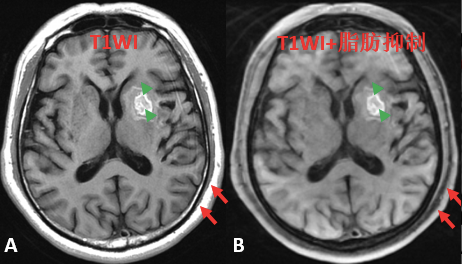

>> 脂肪抑制扫描:

有时病变在 T1WI 上表现为高信号,此时需要进行「脂肪抑制扫描」来判断是脂肪成份还是其他成份,脂肪抑制顾名思义就是将脂肪抑制掉(从高信号变成低信号),而其他的非脂肪成份不会被抑制(如出血)。

进行脂肪抑制另外一个目是为了增强扫描,如果病变内有脂肪呈高信号,会干扰增强扫描后强化程度的判断,在后面增强扫描会介绍。

图片

图 3. 左侧基底节区血肿:A 和 B 分别为 T1WI 和 T1WI 加脂肪抑制序列;T1WI 显示左侧基底节区高信号(绿色箭头);在 T1WI 脂肪抑制仍呈高信号(绿色箭头),提示不是脂肪组织;而皮下脂肪组织在 T1WI 呈高信号(红色箭);在 T1WI 脂肪抑制序列呈低信号(红色箭)